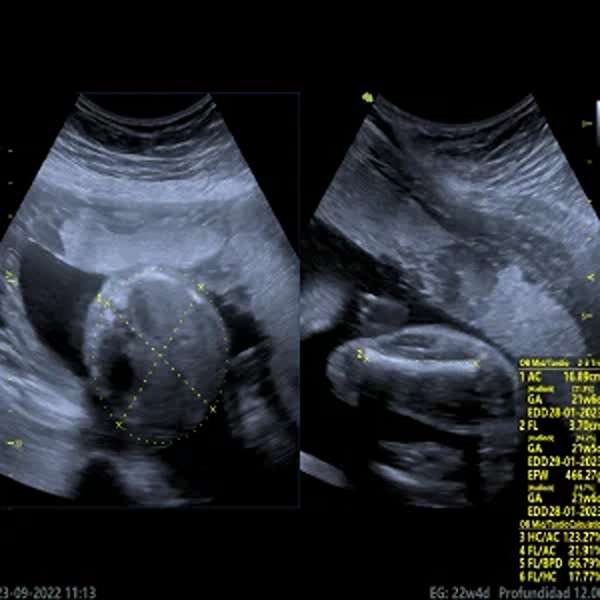

Ecografía Obstétrica

La ecografía obstétrica es un estudio por ultrasonido que permite evaluar el desarrollo y bienestar del bebé durante el embarazo. Se utiliza para confirmar la gestación, determinar la edad gestacional, monitorizar el crecimiento fetal, detectar malformaciones congénitas y controlar la cantidad de líquido amniótico y la placenta. Dependiendo de la etapa del embarazo, puede realizarse por vía abdominal o transvaginal. Es un procedimiento seguro, indoloro y fundamental para el seguimiento prenatal, garantizando un control adecuado tanto de la madre como del bebé.